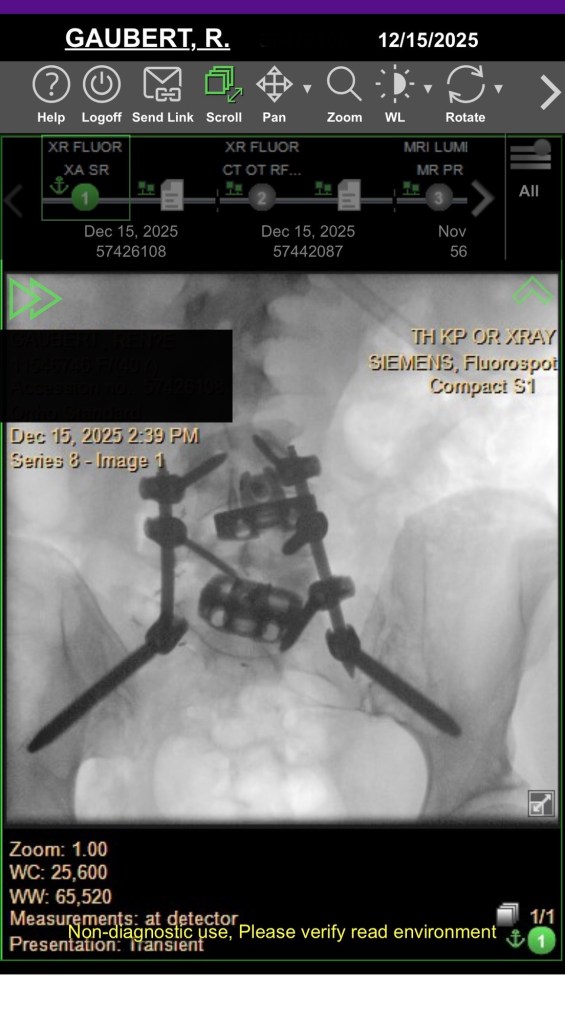

At my 3-month post-op appointment, my surgeon lifted all my restrictions and said I can return to all activity, “just listen to [my] body.” She measured my X-rays (above) and said my lumbar curve decreased 20 degrees, and the thoracic is the same. Also, I grew half an inch. I showed her the scoliosis program I found in New Hampshire, and she was all for it. I’ve booked a furnished apartment in New Hampshire 4/20-5/31 and scheduled the 12 sessions of treatment at the PT clinic there. I’m hopeful that will help with my back pain, and maybe even reduce my thoracic curve. And right before that, I’ll be attending Bionicon!